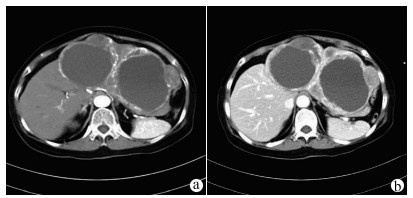

Research advances in diaphragmatic hernia after thermal ablation for primary liver cancer

Yurong ZHANG, Xiaodong WANG, Xiaoning ZHU, Jing WANG

2021, 37(12): 2939-2942. DOI: 10.3969/j.issn.1001-5256.2021.12.043

Abstract(915) HTML (467) PDF (1883KB)(49)

Abstract:

Thermal ablation, including radiofrequency ablation and microwave ablation, is a frequently used method for local treatment of primary liver cancer with a marked clinical effect, and it has been widely used in clinical practice in recent years. Diaphragmatic hernia is a rare complication of thermal ablation, but its incidence rate tends to gradually increase in recent years. This article reviews the cases of diaphragmatic hernia after thermal ablation for primary liver cancer in China and globally and elaborates on possible risk factors, diagnosis and treatment, and prevention strategies, so as to improve the understanding of diaphragmatic hernia after thermal ablation for primary liver cancer among clinicians and achieve the goal of preoperative prevention, rapid diagnosis and intervention, and reduced mortality rate.